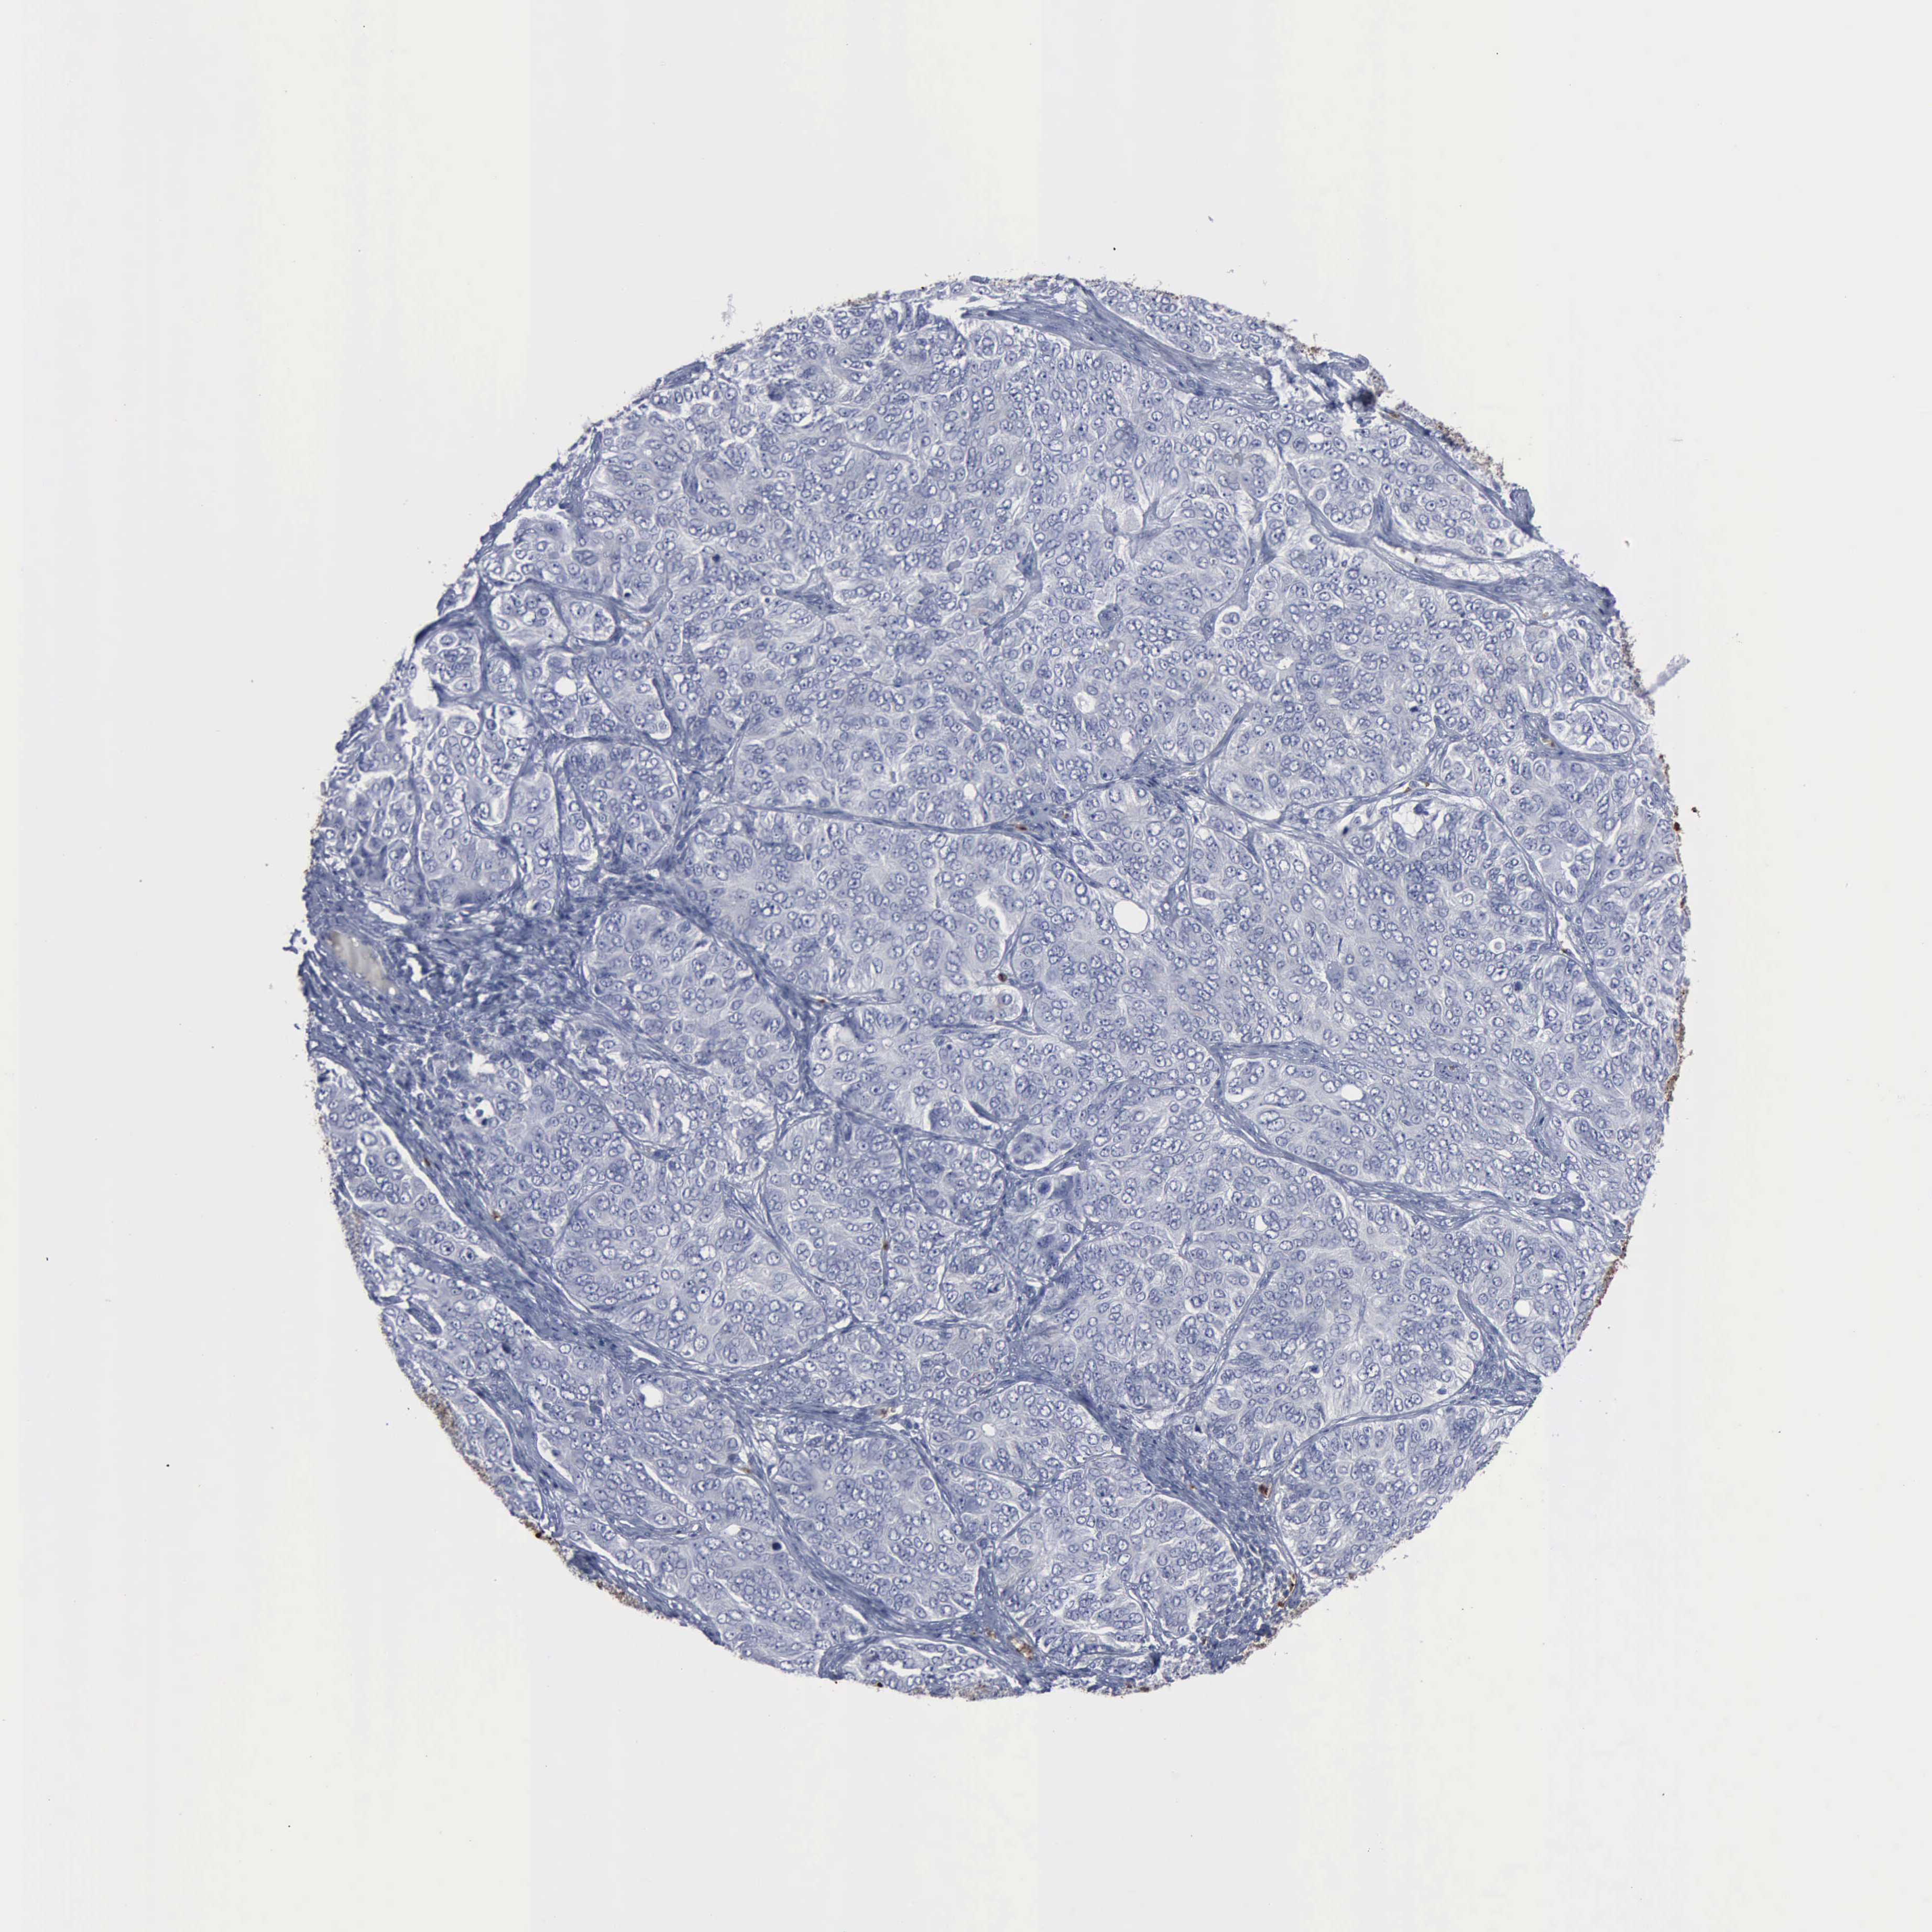

OVARIAN CANCER - Protein expressioni

A mouse-over function shows sample information and annotation data. Click on an image to view it in a full screen mode. Samples can be filtered based on level of antibody staining by selecting one or several of the following categories: high, medium, low and not detected. The assay and annotation is described here.

Note that samples used for immunohistochemistry by the Human Protein Atlas do not correspond to samples in the TCGA dataset.

Antibody stainingi

Antibody staining in the annotated cell types in the current human tissue is reported as not detected, low, medium, or high, based on conventional immunohistochemistry profiling in selected tissues. This score is based on the combination of the staining intensity and fraction of stained cells.

Each image is clickable and will lead to virtual microscopy that enables deeper exploration of all samples and also displays staining intensity scores, fraction scores and subcellular localization as well as patient and tissue information for each sample.

Antibody CAB000361

Cystadenocarcinoma, mucinous, NOS

Carcinoma, endometroid

Cystadenocarcinoma, serous, NOS